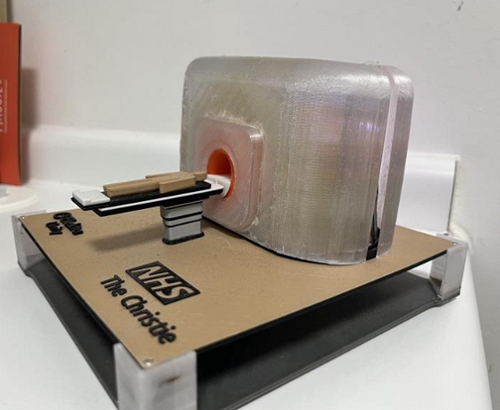

And a special thanks goes to one particular patient who made us a model of our MR-Linac!